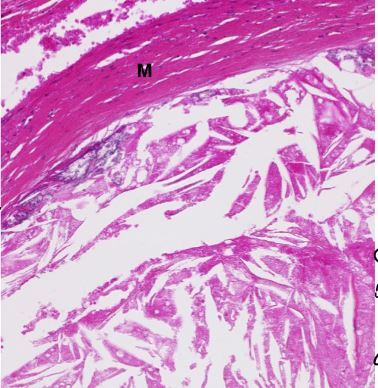

Athérosclérose

occupe entièrement l’intima et une partie de la média (m)

on voit cristaux de cholesterol avec des lipophages (macrophages qui ont mangés du calcium)